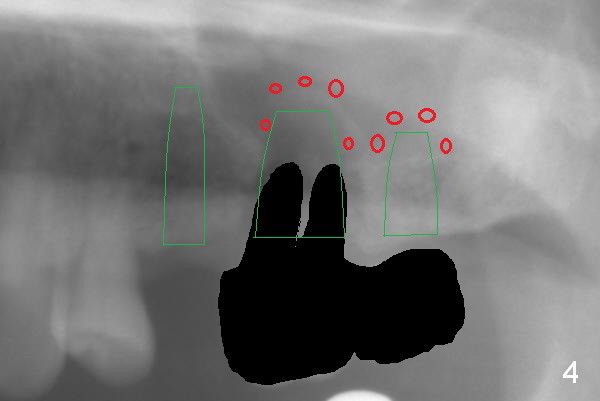

The 72-year-old man will return for #13-15 implantation after that at #2/4 and 28. There is severe wear in the cingula of the upper anterior teeth due to posterior collapse (several missing teeth, residual root and failing restoration, Fig.1). Prior to removal of the cantilever bridge (#14.15), an implant is placed at #13 (Fig.2). If the defect at #14 is too large after extraction, an implant is placed at #15 with an immediate provisional bridge (Fig.3 white line). Otherwise a large implant (possibly Tatum tapered) will be placed at #14 (Clindamycin) with splinted immediate provisional (Fig.4). Allograft is expected for sinus lift at #14 and 15 (Fig.3,4 red circles with Osteogen in 3:1 ratio). For socket preservation at #14, mix equal amount of allograft and Osteogen (Fig.3 pink), followed by Collagen plug (yellow) and the pontic of the provisional bridge. Prepare PRF (3-4 tubes of blood, one of them to be made for a plug).